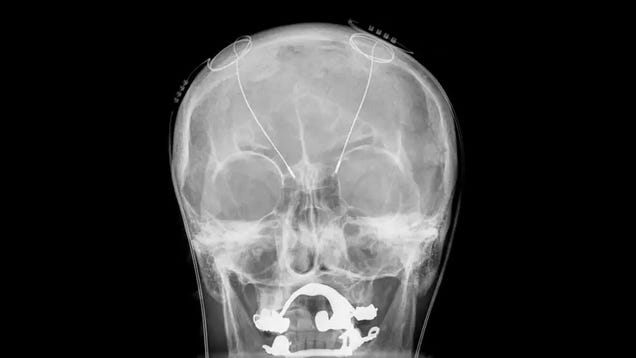

Modern medicine has extended our lives and reduced suffering in all kinds of ways. Many of the impactful interventions we have available today have been around for a long time, though, such as antibiotics, most painkillers, and various forms of cancer screening. But every once in a while, scientists do come up with…

Source: Gizmodo – 5 Real Medical Treatments That Sound Like Sci-Fi